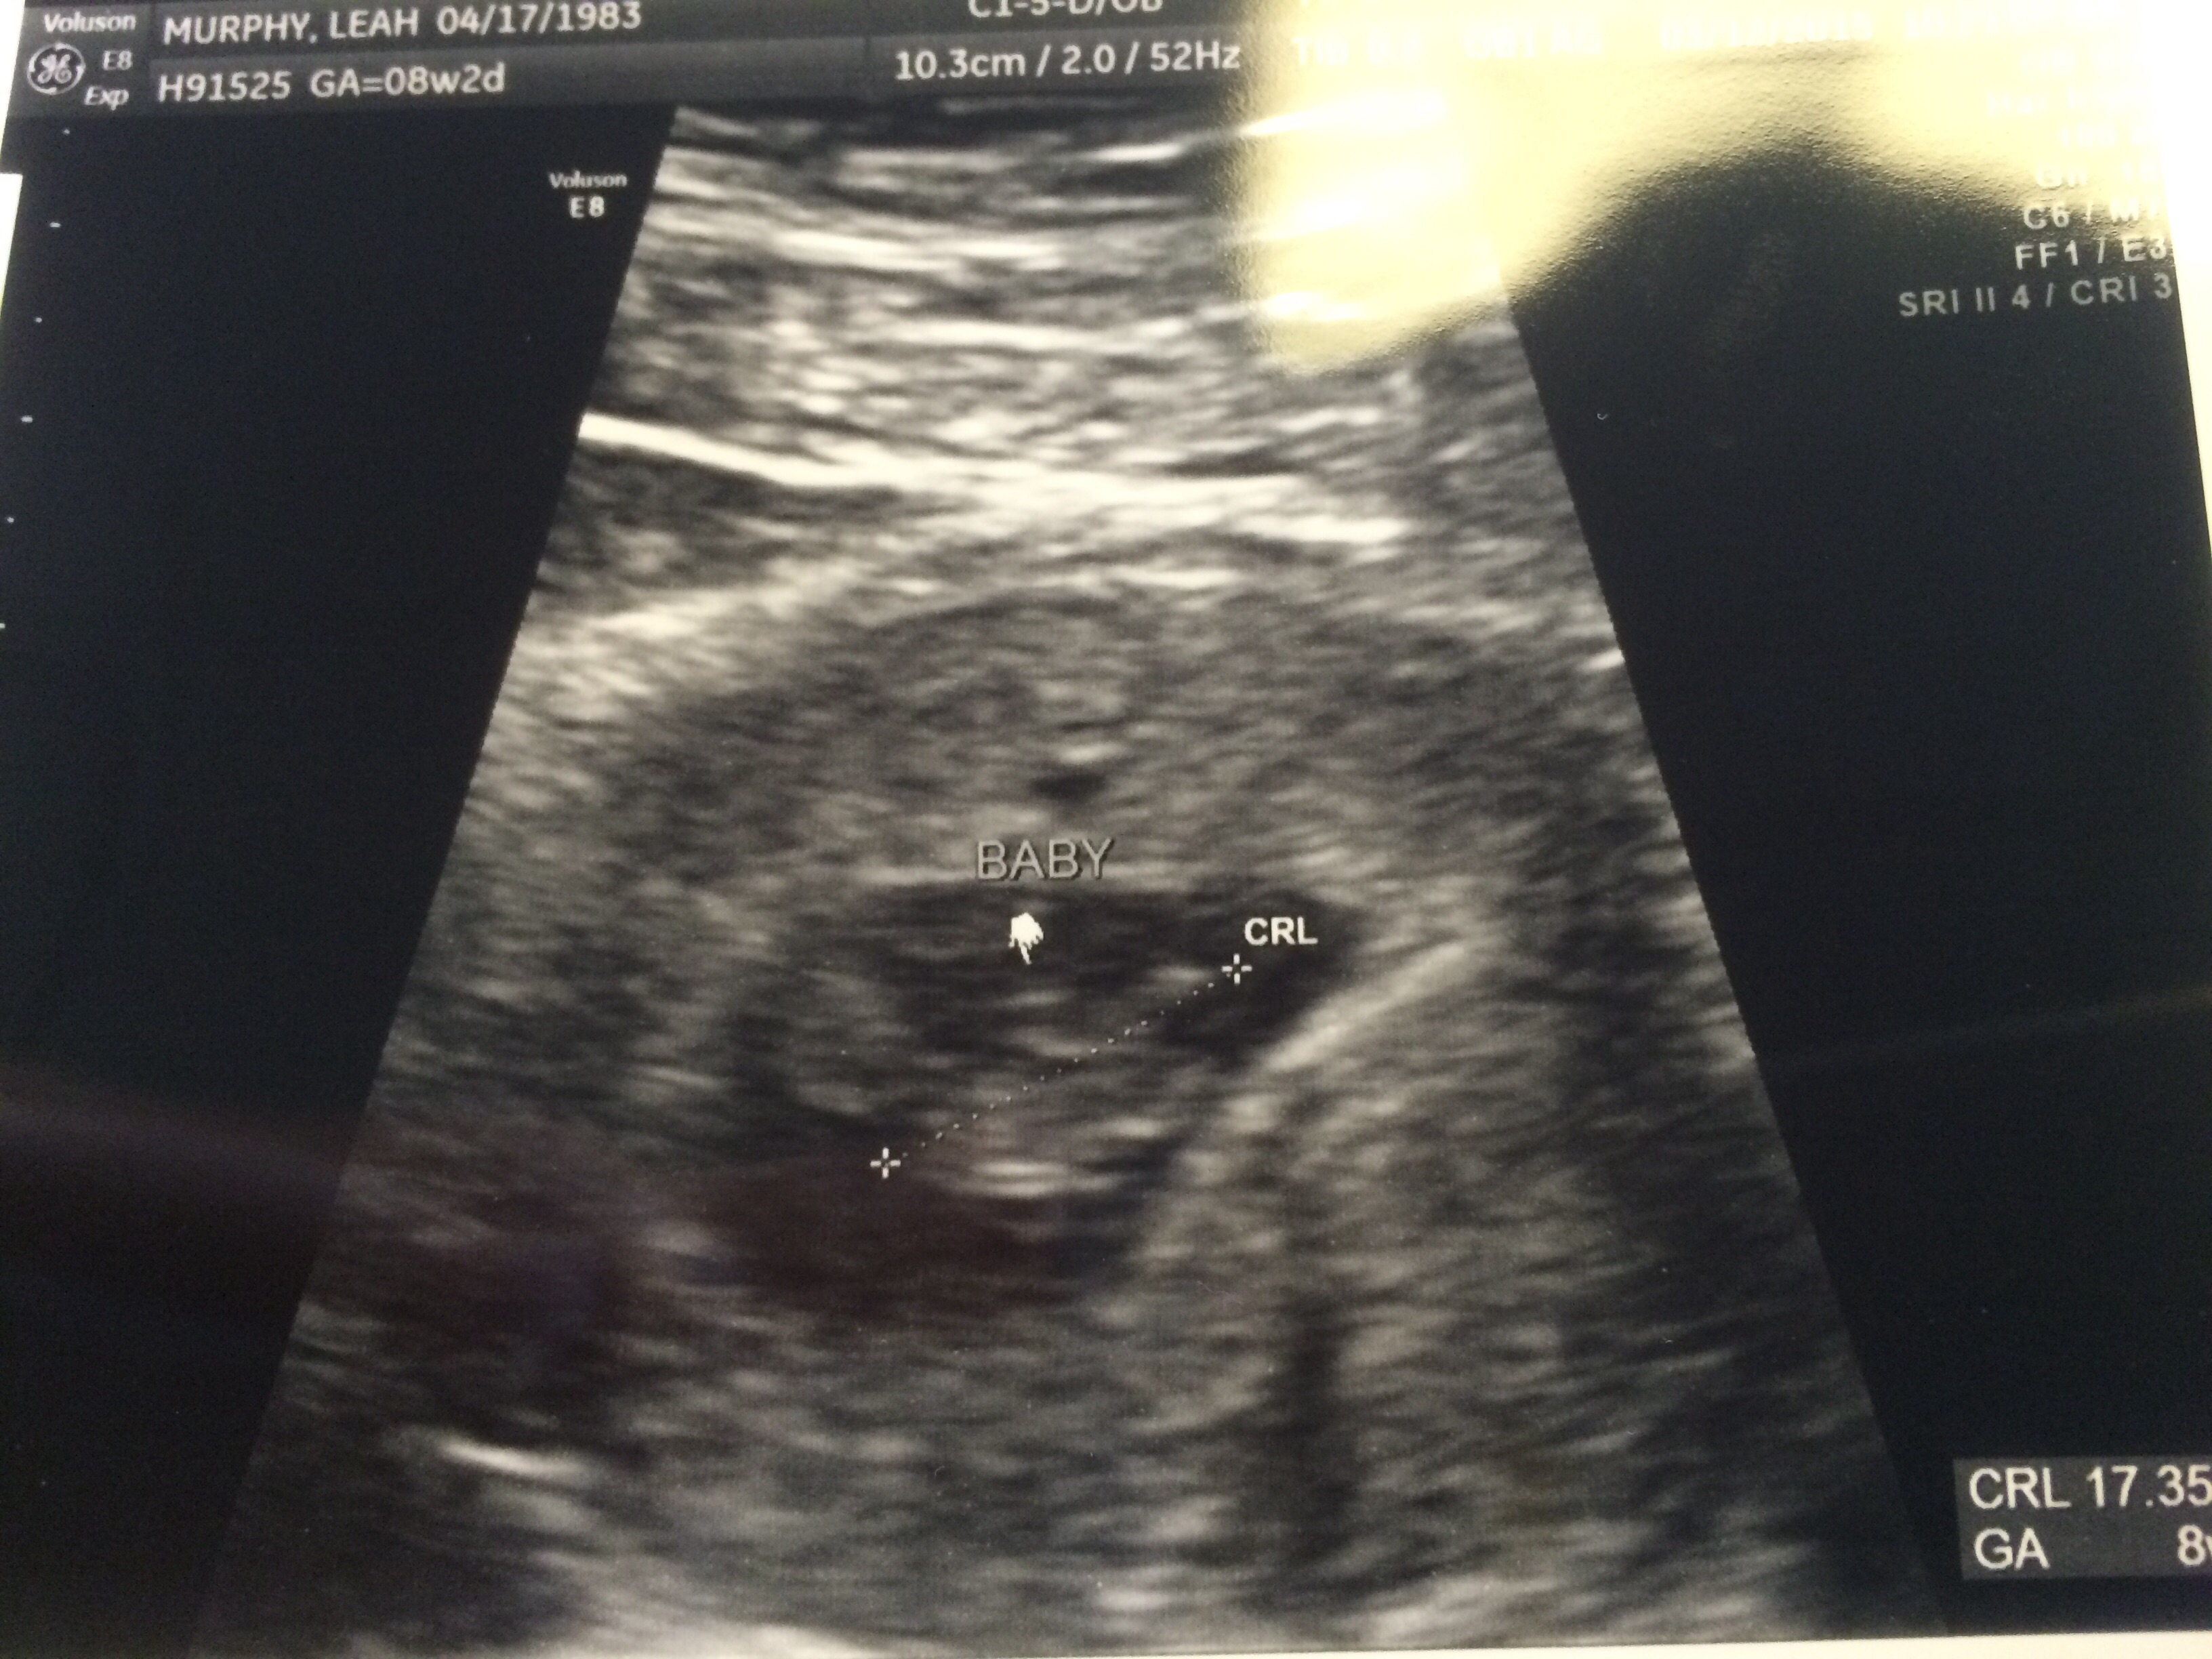

I wasn't going to post mine, but what the hell. Here is my little jellybean a week ago, at 8 weeks and 6 days. They gave me a regular-looking ultrasound picture and two of these freaky 3D ones.